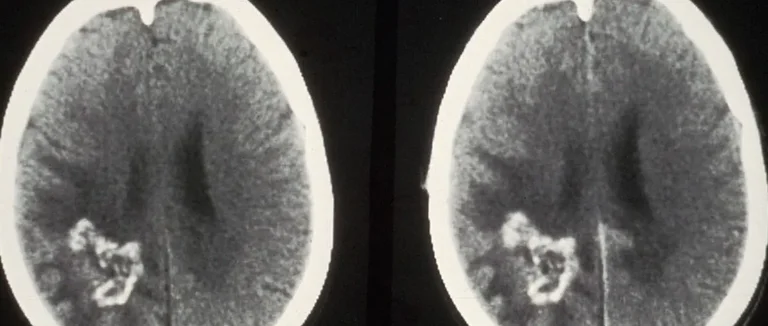

Caractéristiques d'imagerie des différents types de tumeurs

Sur un scanner CT, les tumeurs cérébrales se montrent différemment. Les tumeurs solides se rehaussent avec le produit de contraste. Les tumeurs kystiques ou nécrotiques ont des zones hypodenses.

L'imagerie CT aide à voir les calcifications et les hémorragies liées aux tumeurs.